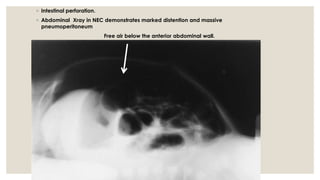

◦ Intestinal perforation.

◦ Abdominal Xray in NEC demonstrates marked distention and massive

pneumoperitoneum

Free air below the anterior abdominal wall.